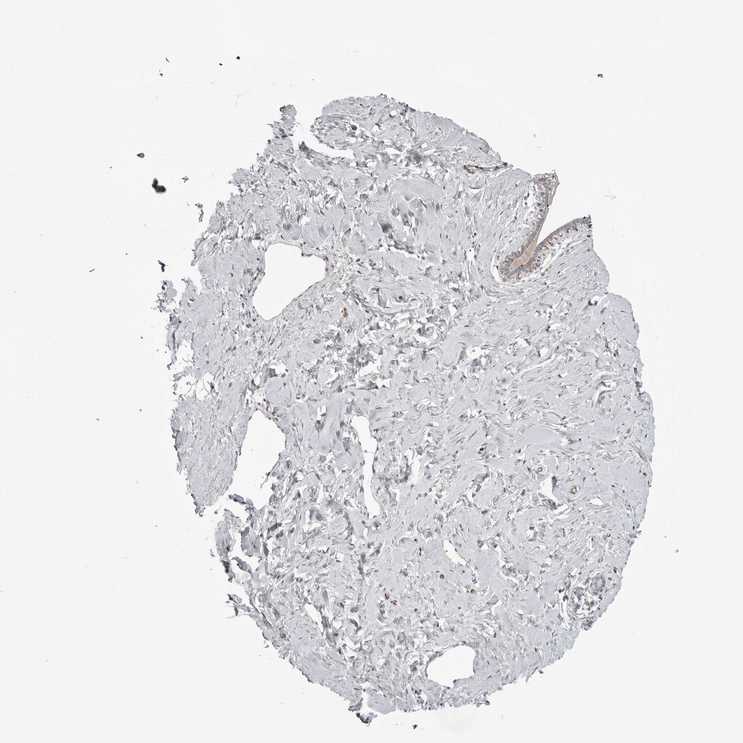

BREAST - Antibody stainingi

Antibody staining in the annotated cell types in the current human tissue is reported as not detected, low, medium, or high, based on conventional immunohistochemistry profiling in selected tissues. This score is based on the combination of the staining intensity and fraction of stained cells.

Each image is clickable and will lead to virtual microscopy that enables deeper exploration of all samples and also displays staining intensity scores, fraction scores and subcellular localization as well as patient and tissue information for each sample.

Antibody HPA048738Antibody CAB026161

Adipocytes LowNot detected

Glandular cells MediumLow

Myoepithelial cells MediumMedium